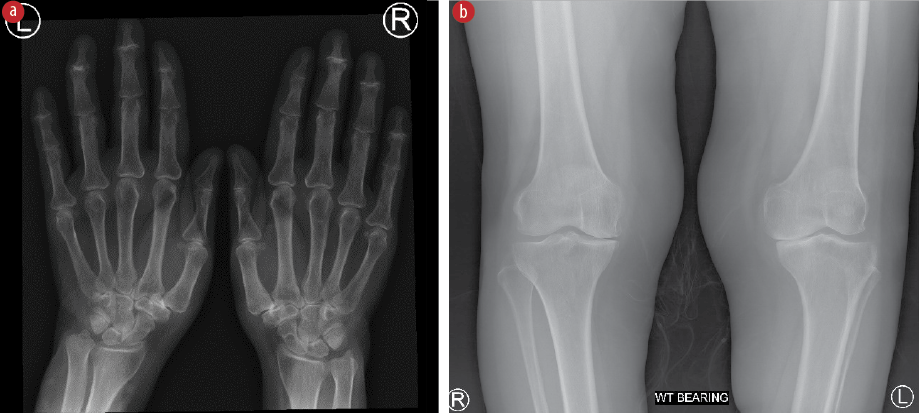

Laboratory investigations showed normal total leukocyte count, urinalysis, creatinine, transaminase, calcium, phosphorus, and uric acid levels. Rheumatoid factor was negative, and C-reactive protein level was mildly raised (10 mg/L; ref < 5). Joint fluid aspirated from the knee and wrist was non-inflammatory. Radiological images post-flare-up revealed signs of osteoarthritis in the proximal and distal interphalangeal joints of the hands, the trapeziometacarpal joint, and both medial tibiofemoral joints [Figure 2].

Figure 2: (A) X-ray image of hands and wrists showing reduced joint space with degenerative changes in proximal and distal interphalangeal joints of the hands, and trapeziometacarpal joints. (B) X-ray of the knees showing reduced joint spaces and degenerative changes in the medial tibiofemoral joints.